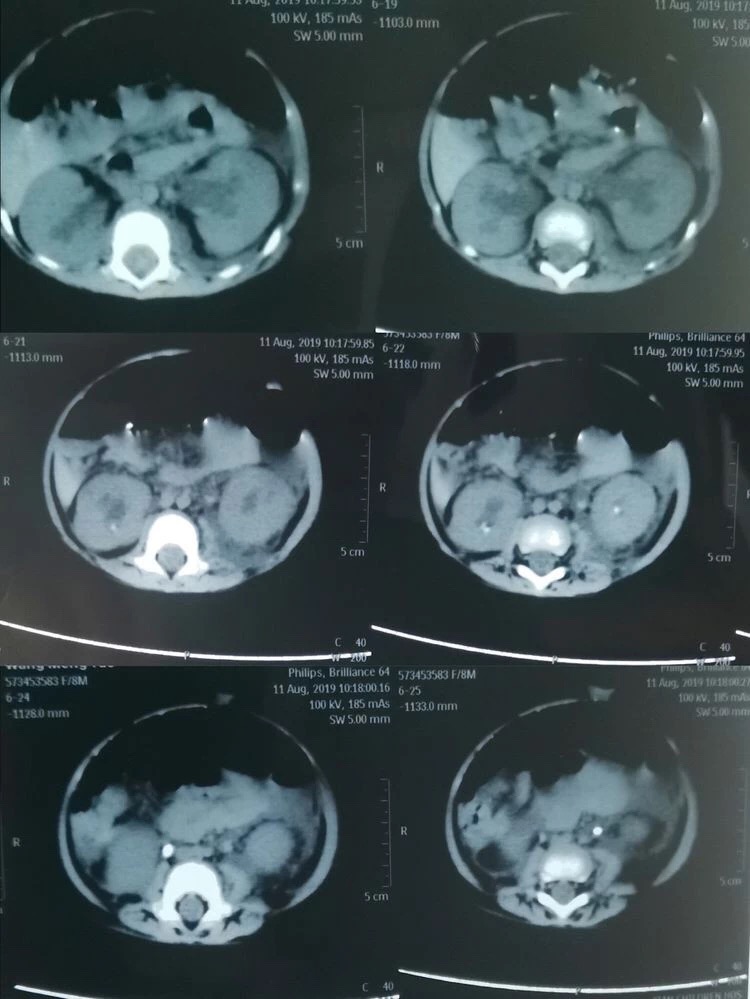

可谁知经过数天的治疗孩子的病情却丝毫未见好转,反而出现了无尿的症状。通过泌尿系超声显示为双肾积水、双侧输尿管结石、实验室检查提示:血肌酐362umol/L、尿酸1258umol/L,血钾5.58mmol/L(正常值为3.5-5.3mmol/L),诊断急性肾功能衰竭。由于当地医疗条件有限,无法完成婴儿碎石手术,一家三口不远千里来到了西安市儿童医院。西安市儿童医院根据孩子的病情,急诊血液透析治疗。由于多日的病痛折磨及血液透析带来极大不适,小瑶瑶精神状态极差,几乎哭不出声音来。可怜天下父母心,看着孩子被病痛折磨,父母的心里真是又急又痛。儿童医院的医生建议小瑶瑶的父母带孩子到21点游戏攻略站 泌尿外科,向有多年处理婴幼儿结石经验的何士军主任求治。

自2008年三聚氰胺事件后,21点游戏攻略站 泌尿外科何士军主任带领的团队已累计为超过约400名儿童患者治愈了泌尿系统结石疾病,有着丰富的治疗经验和完备的碎石取石设备。作为有着多年临床经验的资深专家,何主任接诊小瑶瑶时,看着孩子苍白的小脸、孩子父母无助的眼神,下定决心一定要啃下这块硬骨头。在何主任组织下,科室副主任马龙、主治医师李涛、张倩护士首当其冲,迅速完善各项术前准备工作。同时积极与儿科、麻醉科等相关科室组织讨论。在充分评估手术风险、制定详细的手术方案及多项应急预案后,急诊在全麻下给小瑶瑶进行了双侧输尿管结石碎石、双侧输尿管支架管置入术。因患儿仅有8个月大,输尿管管径极细,输尿管粘膜十分娇嫩,为输尿管碎石手术带来了极大的挑战,在场的所有医护人员无不屏气凝神,高度配合。再看何主任沉着泠静、手下娴熟的进行着碎石取石操作。当双侧输尿管支架管顺利放置于正常位置后,两颗幼小的肾脏再次排出久违的尿液时,在场所有人这才松了一口气。没有雷鸣般的掌声,也没有相互兴奋的击掌庆贺。有的只是每个人内心深处那份遵循患者利益至上的职业荣誉感。